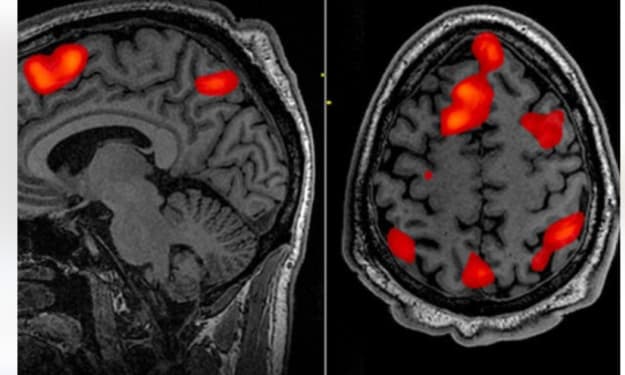

This makes you particularly sensitive to changes in brain health. Previous studies have shown that language skills are often one of the first skills to be weight under conditions such as dementia and Parkinson's disease. This task is also strongly based on the prefrontal cortex, a brain area that is particularly susceptible to aging and disease.